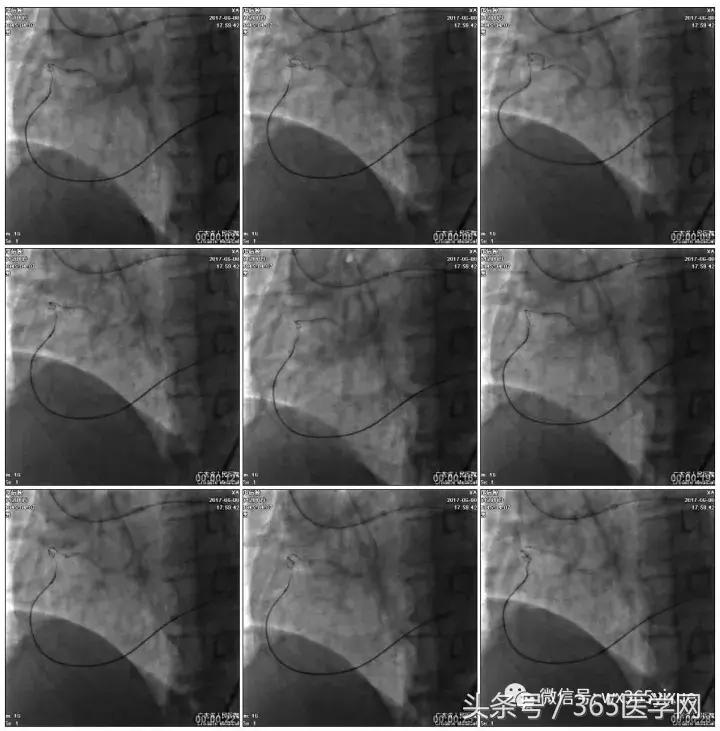

Fielder XT-A,Gaia First ---在微导管支撑下通过闭塞病变

LCX植入支架

2.0*10mm球囊

2.75*22mm药物支架